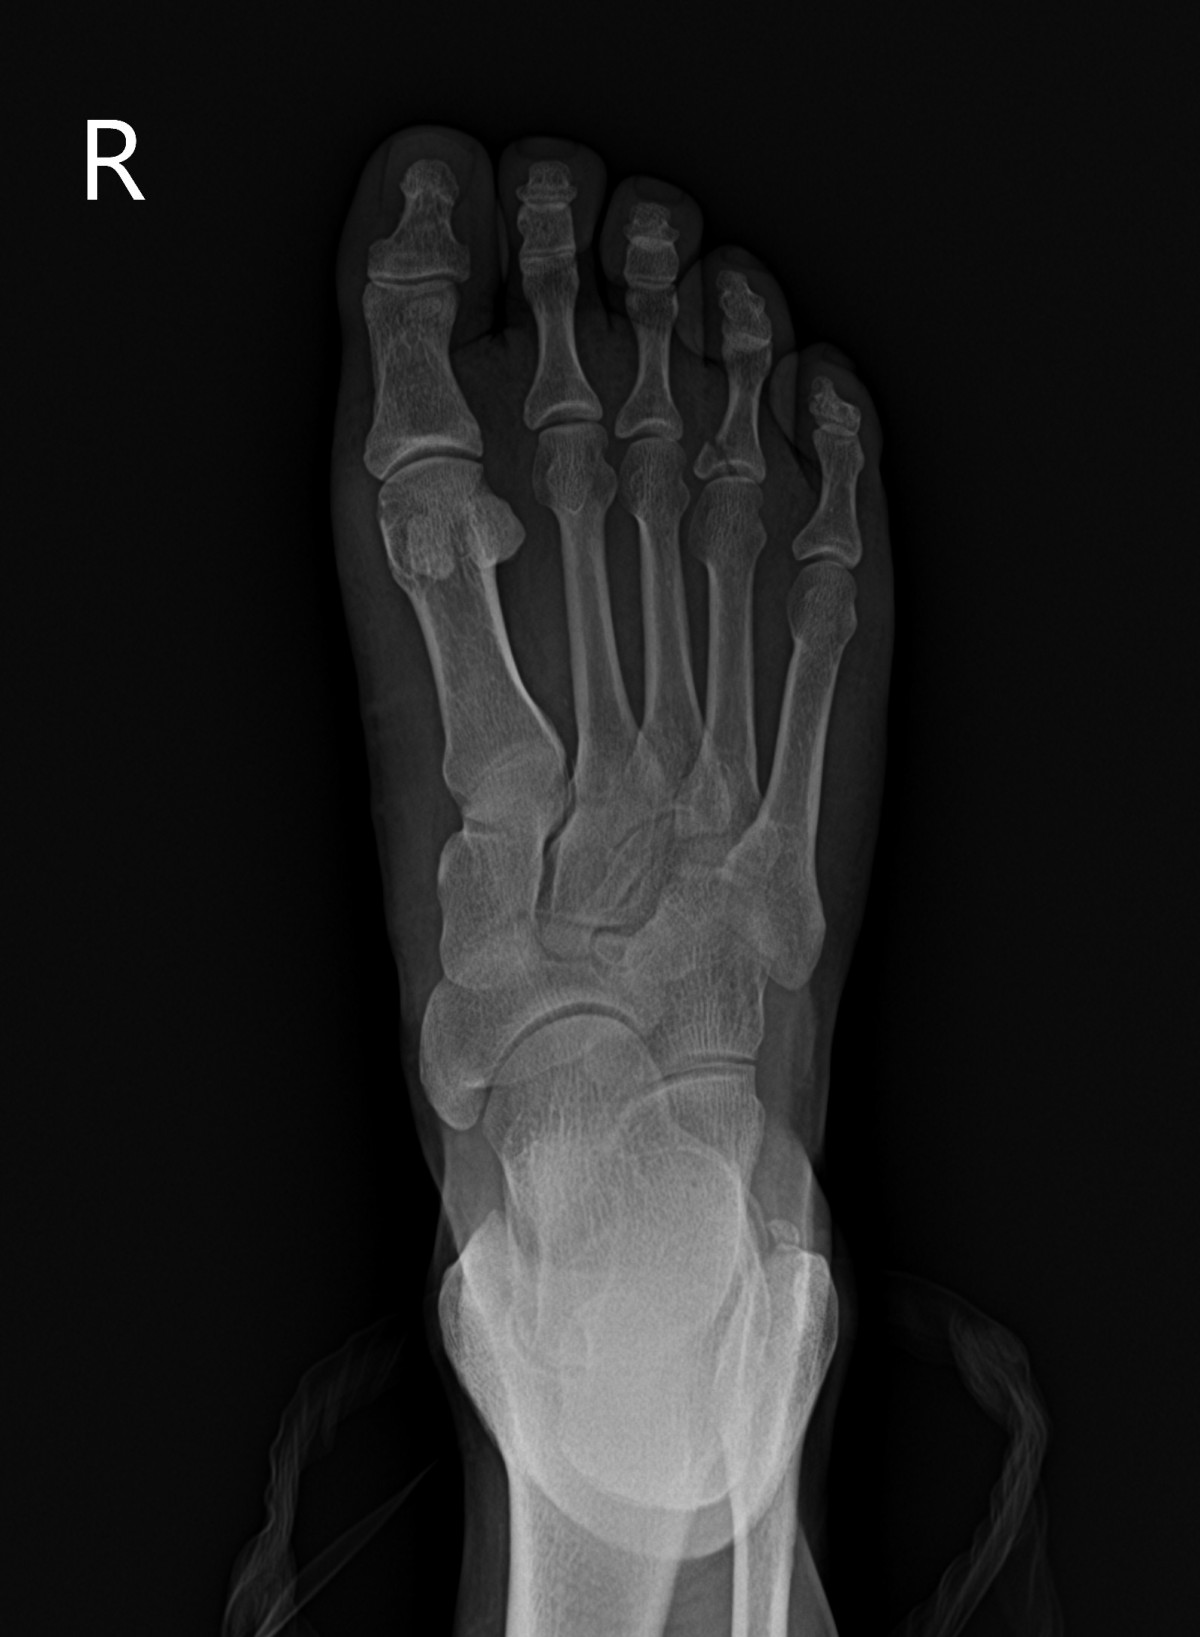

정지영원장님 발가락 골절 수술 윤주O 환자

dae765e4d9ac96aee867c9d6292d8784_1758008258_0191.jpg